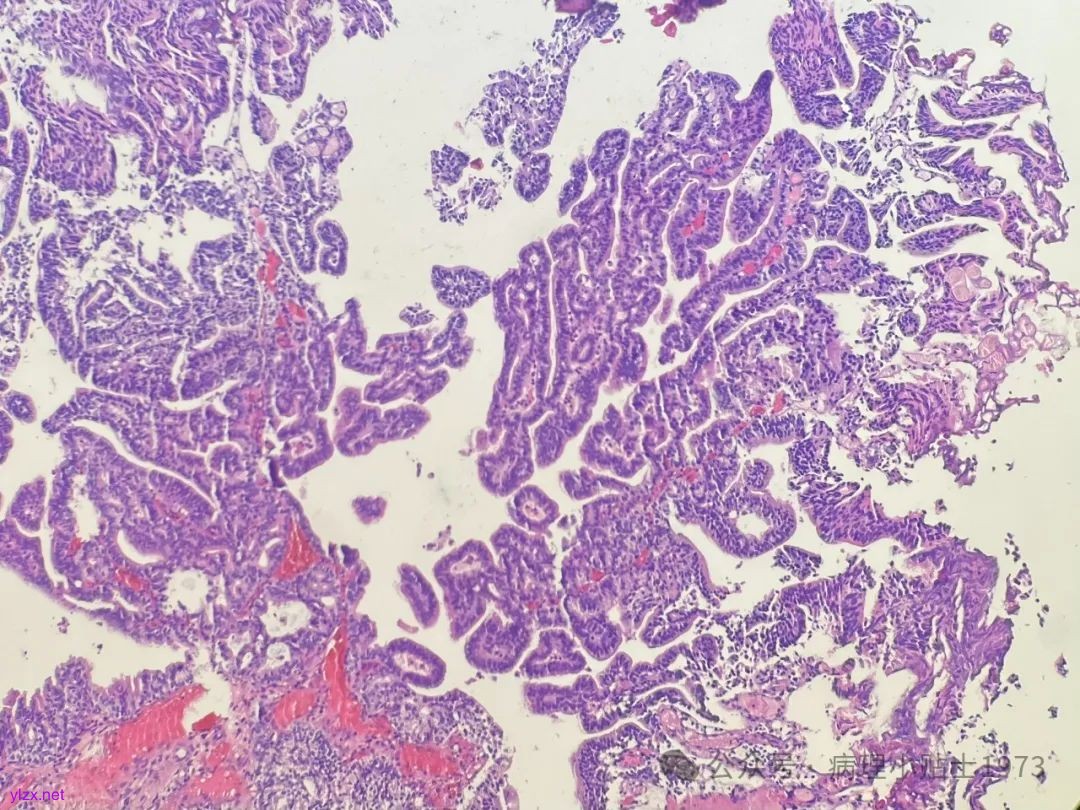

中年男性,膀胱左侧壁结节,诊断考虑?

【简要病史】反复血尿半月余。CT盆腔平扫及增强提示:膀胱左侧壁结节。

诊断:非浸润性乳头状尿路上皮癌伴显著腺性分化

问题一:本病例出现了显著的腺性分化,不要误诊为单纯的腺癌。仔细寻找,仍然可以见到复层排列的经典尿路上皮癌成分。